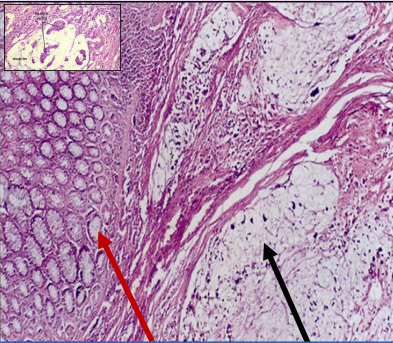

Adenocarcinoma of colon

MALIGNANT TUMOR formed of irregular acini infiltrating the submucosa and muscle layer. Malignant cells vary in size and shape

Red: normal mucosal glands Black: Malignant glands

Malignant